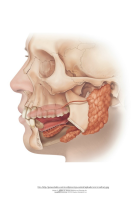

Näo ja suu anatoomia

1